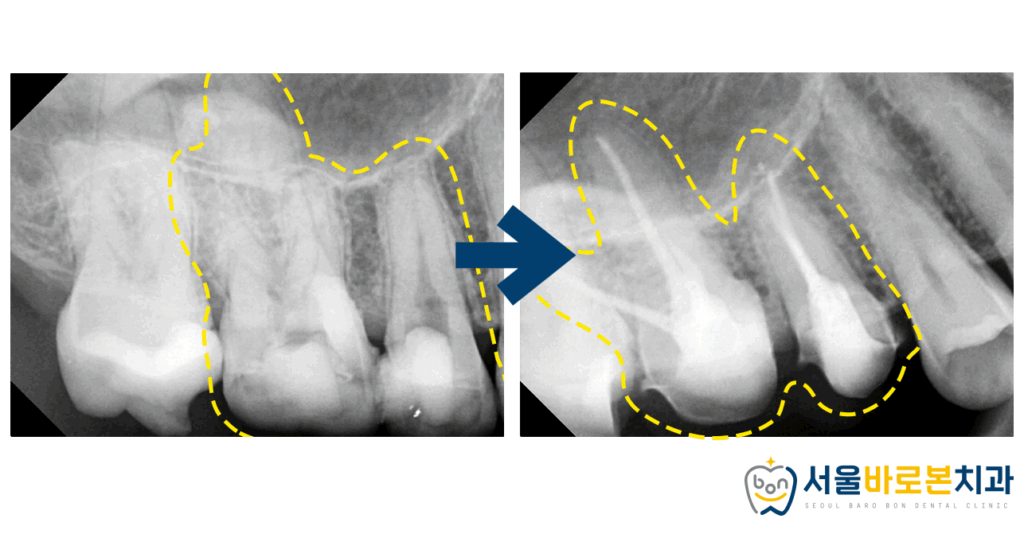

방사선 사진상에서도

확실하게 확인이 됩니다.

때워져 있던 금 인레이 아래로

2차 충치가 진행되고 있었는데요.

치아 내부의 신경까지 썩거나

혹은 그 근접한 깊이까지 썩어 들어가면

더 늦기 전에 금광동신경치료를 통해

자연치를 보존해야 합니다.

이 시기가 너무 늦어지게 되면

발치까지 이어질 수 있다는 사실,

알고 계셨나요?ㅠㅠ